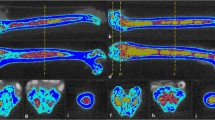

Histological results

CD34 immunohistochemical staining showed that the MVD in the diabetic group was lower than that in the control group at the 16th week (Z = -3.785, P < 0.01). HE staining showed that the number of adipocytes in the diabetic group was higher than that in the control group (t = 1.125, P = 0.037) (Fig. 4). HE staining of the lumbar spine in the diabetic group showed a decrease in the area and number of trabecular bone(Figure 5). The Tb.Ar and Tb.N in the diabetic group were lower than those in the control group (t = -4.540, P = 0.016 ; t = -2.827, P = 0.043).

Decrease in the number of adipocytes (yellow arrow) in the control group (4a). Increase in the number of adipocytes (yellow arrow) in the diabetic group (4b) (HE staining; original magnification, ×200). Microvessels (red arrow) are sparser in the diabetic group (4d) than in the control group (4c) (CD34 staining; original magnification, ×200)

Correlation analysis

In Fig. 6, spearman correlation analysis showed that MVD was negatively correlated with median intensity, quantile50, and quantile75 (r = -0.504, P = 0.023; r = -0.490, P = 0.028; r = -0.541, P = 0.014; 95% CI). The number of adipocytes was negatively correlated with PC 14:0–16:0 and PC 18:1–20:1 (r = -0.501, P = 0.025; r = -0.467, P = 0.038; 95% CI). The FF ratio was positively correlated with PC 15:0–18:1 (r = -0.457, P = 0.043; 95% CI), and Kep was negatively correlated with PC 14:0–16:0 (r = -0.478, P = 0.033, 95% CI). The correlations between the remaining parameters were not statistically significant (P > 0.05).